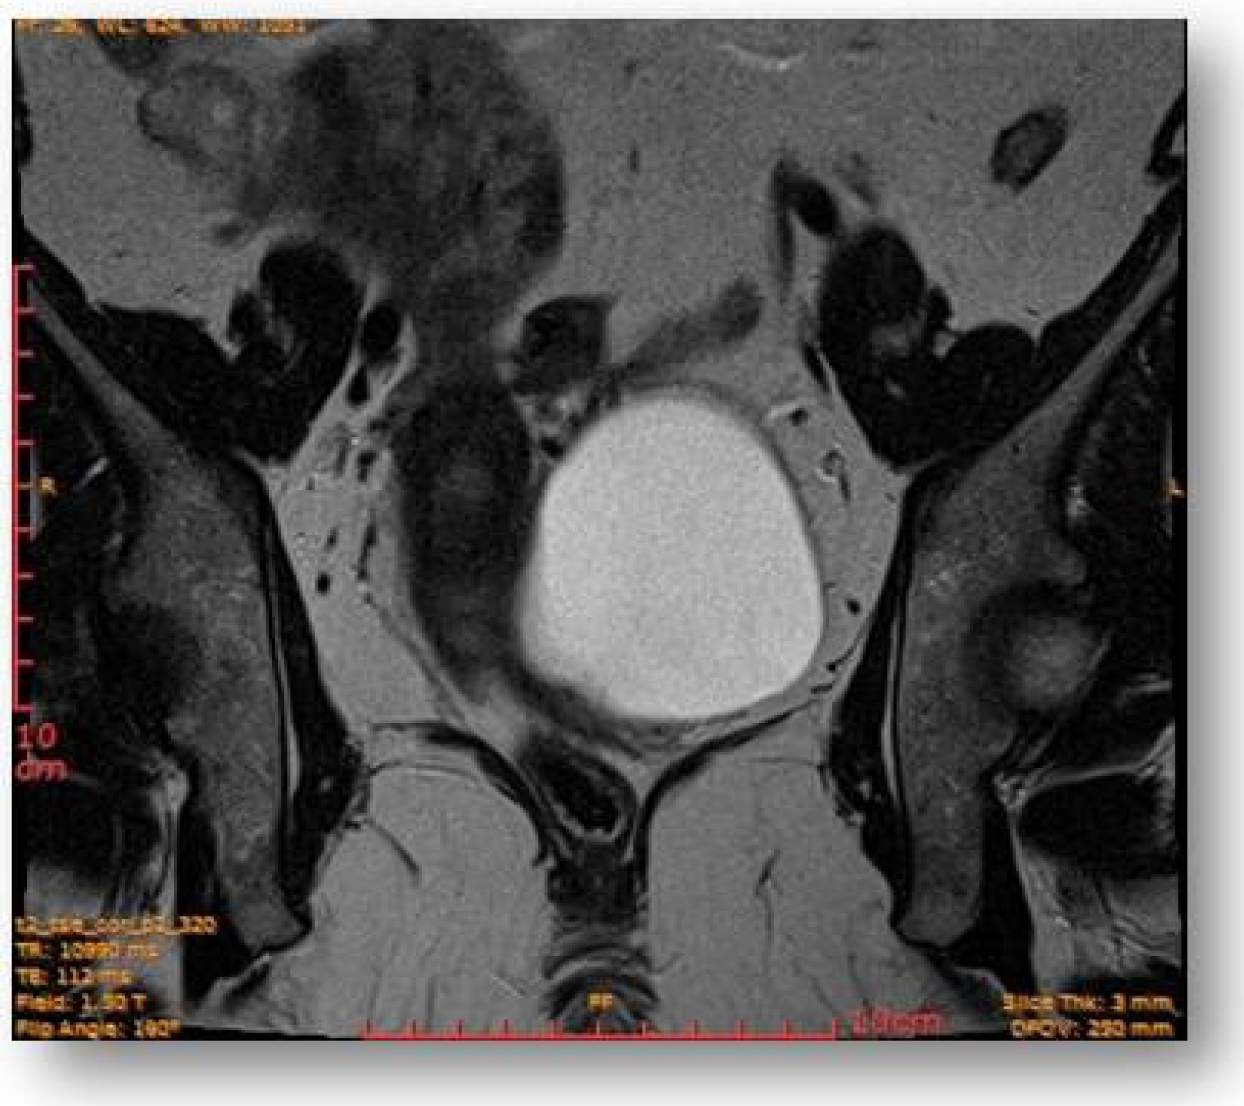

2.4. Diagnostic Assessment and Investigations